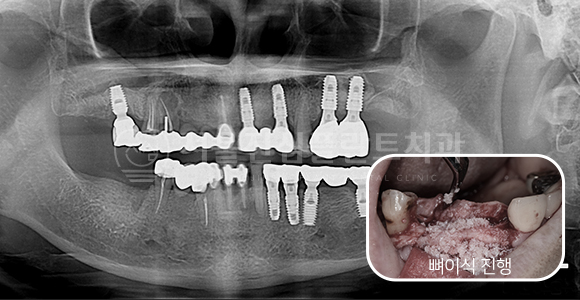

임플란트 재수술 + 상악동 거상술

-

BEFORE

AFTER

상악동 거상술 측방접근법 + 기존 임플란트 제거 후 재수술